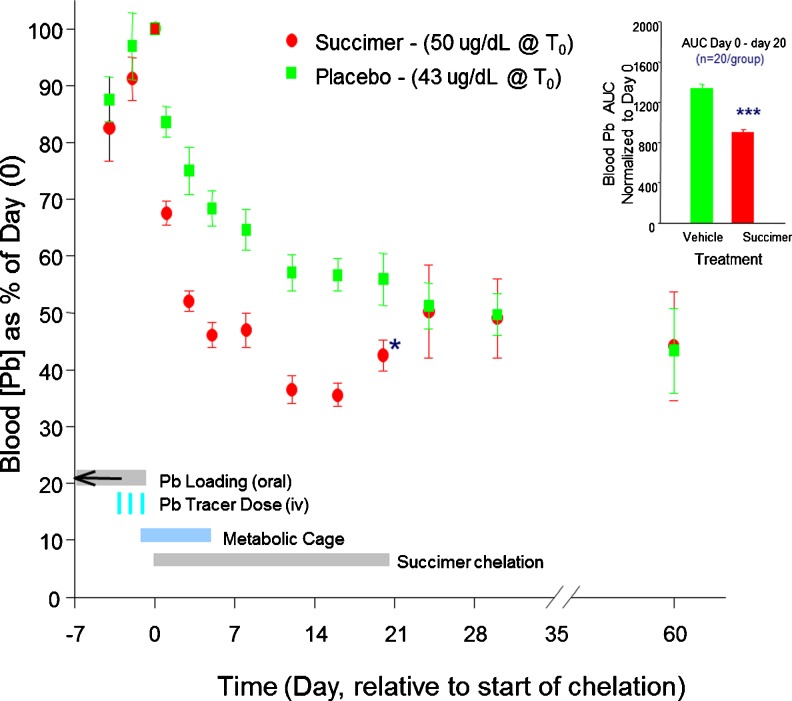

Figure 3 shows the relative reduction in blood lead levels over the first course of chelation, with blood lead levels normalized to the starting (chelation day 0) blood leads of ∼43 to 50 mcg/dL in the two treatment groups. The data clearly demonstrate a reduction in blood lead levels with chelation, though notably the reduction is most dramatic over the first several days of treatment.

Fig. 3.

Mean ± SE blood total lead levels (as % of day 0 pretreatment values) in succimer and placebo-vehicle-treated 1-year lead-exposed monkeys over the course of the first chelation treatment (days 0–20) and beyond. Placebo and succimer group n = 21–23/group for days 24 to 20, and n = 11/group for days 24 to 60. (Inset) The mean ± SE integrated area under the curve (AUC; days 0 to 20) for the placebo vehicle and succimer groups. ***Statistically different (p < 0.001) from placebo group (comparisons performed only on treatment day 20 and on AUC data). For reference, blood lead levels on day 0 were 43 and 50 mcg/dL for the placebo and succimer groups, respectively (p = 0.08). Data from Smith et al. [11]. [Reprinted from Toxicology and Applied Pharmacology with permission from Elsevier]

It should be noted that while there is a dramatic drop in blood lead levels in the succimer-treated group with treatment, there is also a dramatic drop in the placebo-vehicle group, reflecting the efficacy of the cessation of lead exposure alone. However, when one looks at the integrated blood lead level over the treatment period, which is the area under the curve shown in Fig. 3, there is an overall substantial and significant reduction in blood lead in the succimer versus vehicle group, as expected. It is noteworthy, however, that there is a substantial rebound in blood lead levels in the succimer-treated group at the cessation of treatment, such that if one assessed chelation efficacy a few days after treatment ended, the data would indicate no measurable difference between the succimer and vehicle groups (Fig. 3). This raises the issue that assessment of chelation efficacy based on blood lead reduction may depend in part on when exactly blood lead levels are evaluated relative to chelation.